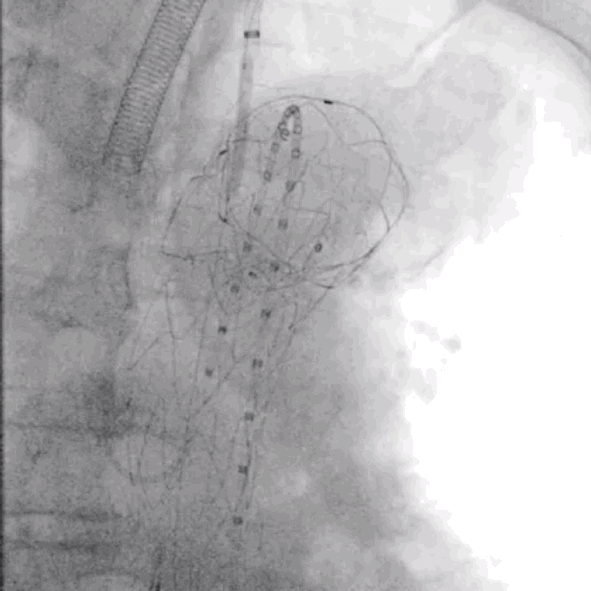

2.右股动脉置鞘交换Lunderquist导丝后,经右侧股动脉上华脉泰科PTBS3834180胸主动脉覆膜支架至左颈总动脉后缘位置,完全覆盖病变段,释放支架。

泥鳅导丝怎么用符伟国/王利新教授团队:0.035"普通泥鳅导丝进行胸主动脉弓上分支原位开窗的病例分享_https://www.jmylbn.com_新闻资讯_第10张

近端定位LCCA根部后缘

泥鳅导丝怎么用符伟国/王利新教授团队:0.035"普通泥鳅导丝进行胸主动脉弓上分支原位开窗的病例分享_https://www.jmylbn.com_新闻资讯_第11张

释放大支架

泥鳅导丝怎么用符伟国/王利新教授团队:0.035"普通泥鳅导丝进行胸主动脉弓上分支原位开窗的病例分享_https://www.jmylbn.com_新闻资讯_第12张

释放近端裸支架